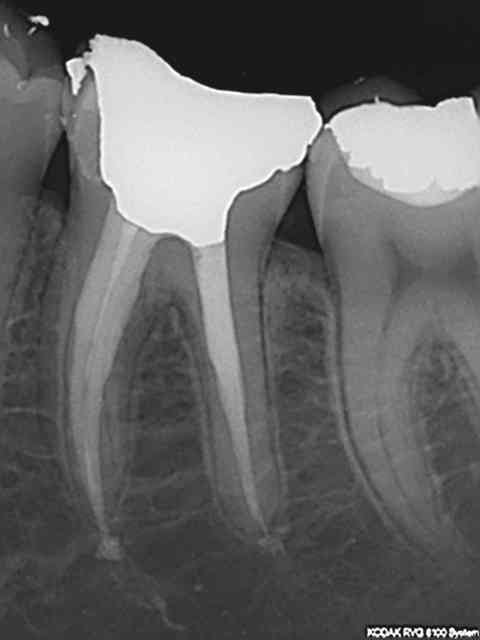

Parfois, je pars pour un onlay Emax, et c'est tellement carié que je fais un onlay 3 faces et demi (derniere face avec les cuspides en onlay).

Parfois, je me demande si c'est possible de coter et facturer ca comme une couronne, vu le temps que ca me prend pour bien tout faire.

C'est pour cette raison que je me pose cette question. Il m'arrive souvent de faire des onlays 4 parois.

Est-ce que j'aurai pu les coter comme des couronnes emax ? puisque c'est le meme materiau.

Et concernant la paroi résiduelle... C'est vraiment dans un cas ou on est a un cheveux pas loin de la couronne. Dans ce cas, pourquoi faire en sorte que le patient et moi meme en sortent perdant si il suffit de changer le nom du truc et de faire un truc un peu plus invasif (1 mm) si ca signifi une durabilité plus longue.

J'ai déjà fait des onlays 4 faces avec le même matériaux que ma couronne 4 faces.

En gros on peu maintenant reconstituer la dent avec de l'emax et peu importe vraiment la forme de la taille pour peu qu'elle obéisse à certaine règle.

Le problème c'est que je me dis souvent... Mince, j'ai fait un onlay avec taille de couronne. J'aurai pu gagner plus et le patient aurait pu se faire rembourser mieux !

Quand est-ce que vous transformer un onlay en couronne vous ?